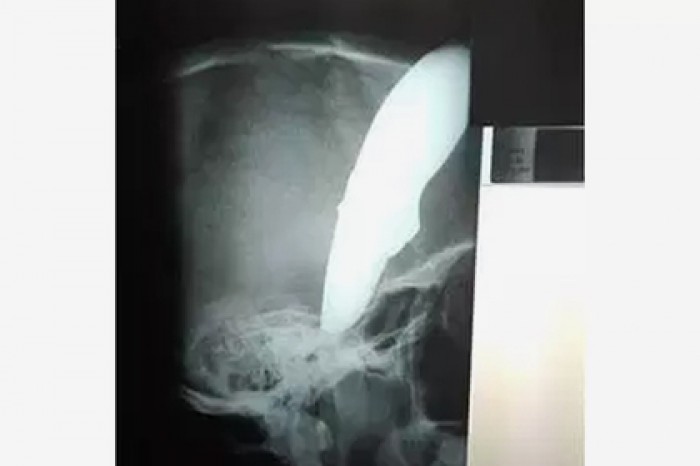

Велосипедист с ножом в голове отбился от преступников и сам приехал к врачу

Житель Кейптауна (ЮАР) Шон Уэйн (Shaun Wayne) пережил нападение преступников и сам приехал в больницу с ножом в голове. Об этом сообщает издание Daily Mail.Инцидент произошел в понедельник, 19 ноября. Мужчина ехал на работу в свой суши-ресторан на велосип